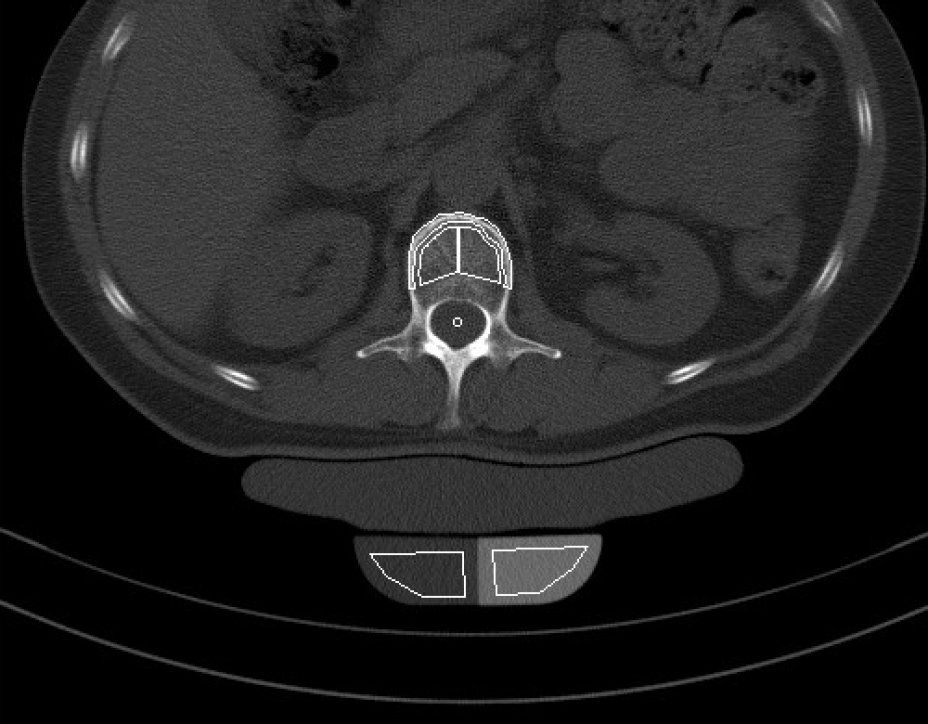

Die Knochendichtemessung mittels Computertomographie (Q.CT) ist eine der genausten Methoden zur Bestimmung der Knochendichte und gilt als Goldstandard. Sie ist sowohl für die Diagnosestellung als auch zur Verlaufskontrolle geeignet. Zur Bestimmung der BMD (engl.: Bone Mineral Density) werden bei der quantitativen Computertomographie ca. 3 bis 4 Scans von der Lendenwirbelsäule angefertigt. Aus der Knochendichte dieser Wirbelkörper wird der Mittelwert ermittelt. Dieser wird dann mit der Knochendichte eines gleichaltrigen Knochengesunden verglichen und in Relation dazu gesetzt. Je nach der Dichte des Knochens wird die Osteoporose dann in mehrere Stadien eingeteilt. Da die Knochendichtemessung (Q.CT) keine Kassenleistung ist, bieten wir die Untersuchung als

IGEL - Leistung an.

Q-CT gestützte Knochendichtemessung